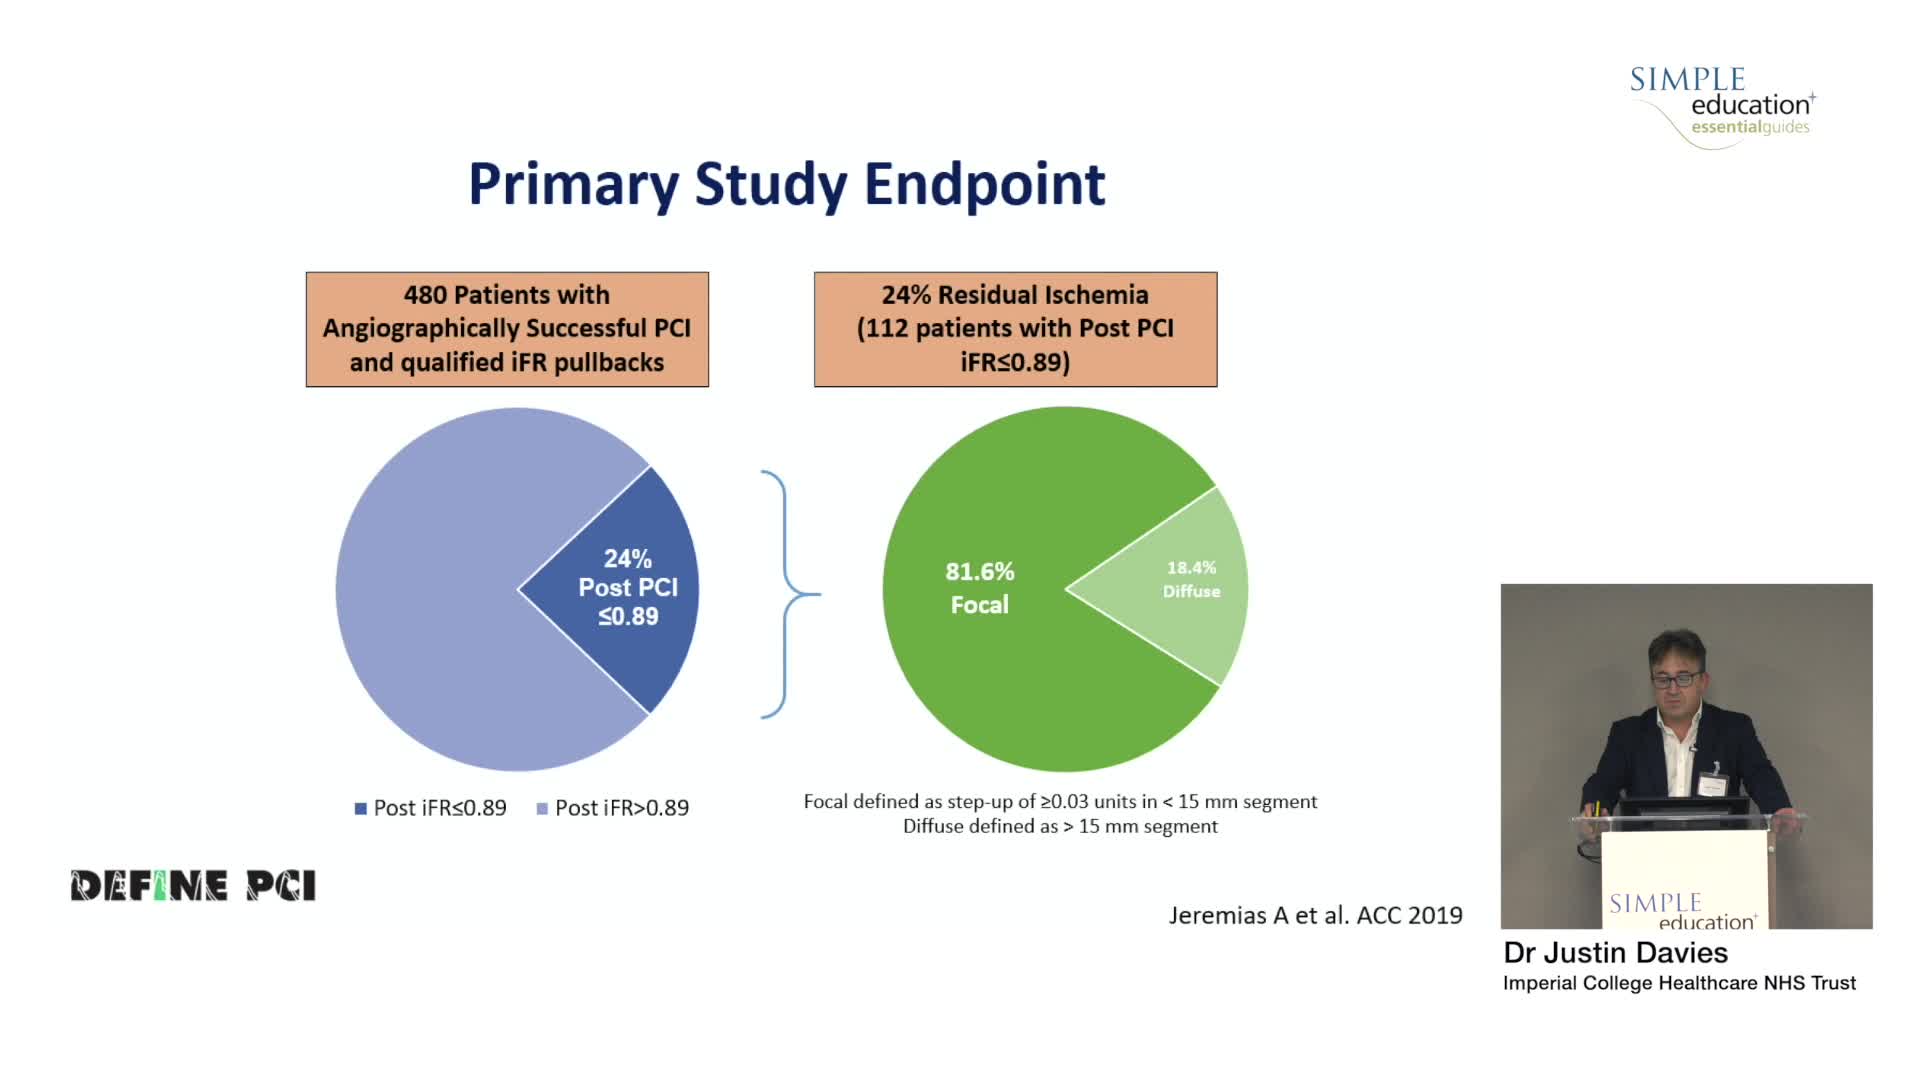

Coronary physiology gate keeper or guide to coronary PCI? Rationale and design of DEFINE-GPS

Essential steps for physiology-based PCI planning and guidance - Dr Allen Jeremias